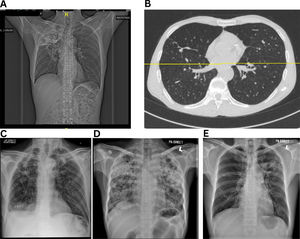

Most studies on PTLD risk are cross-sectional or retrospective, limiting causal inference or identifying early predictors [7]. The absence of simple, scalable diagnostic tools for resource-limited settings further compounds the challenge. Although some studies followed up beyond 6–9 months post-treatment, most focused primarily on spirometry, offering limited insights into PTLD's natural history, and progression [39,40,45]. Imaging remains central to diagnosis: chest radiographs may reveal residual fibrotic bands with volume loss, bronchiectasis, pleural thickening, cavities, or calcifications [46] (Fig. 2), while high-resolution computed tomography (HRCT) provides more detailed characterization [36]. Nevertheless, radiologic severity often poorly correlates with symptoms or functional decline, complicating clinical interpretation [47].

Representative radiographic and high-resolution CT images of patients with microbiologically confirmed pulmonary TB. (A) Extensive right upper lobe volume loss, fibrotic scarring, and tracheal deviation to the right—hallmarks of post-tuberculosis fibrotic lung damage, (B) Bilateral bronchiectasis with dilated bronchi, parenchymal scarring, (C) Cavitary lesions and right upper lobe fibrosis, (D) and (E) Severe fibrosis and bronchiectasis.

Pulmonary function testing complement radiology, often revealing a mixed restrictive/obstructive patterns with predominant airflow obstruction [45]. Yet, spirometry access remains limited in many high TB-burden settings, and longitudinal follow-up beyond lung function impairment assessment is lacking [39]. Moving forward, prospective studies assessing the full spectrum of PTLD and consensus-based diagnostic algorithms are essential. Integration of spirometry and symptom screening, coupled with validated imaging scores into routine post-treatment care, would enable earlier detection and intervention.